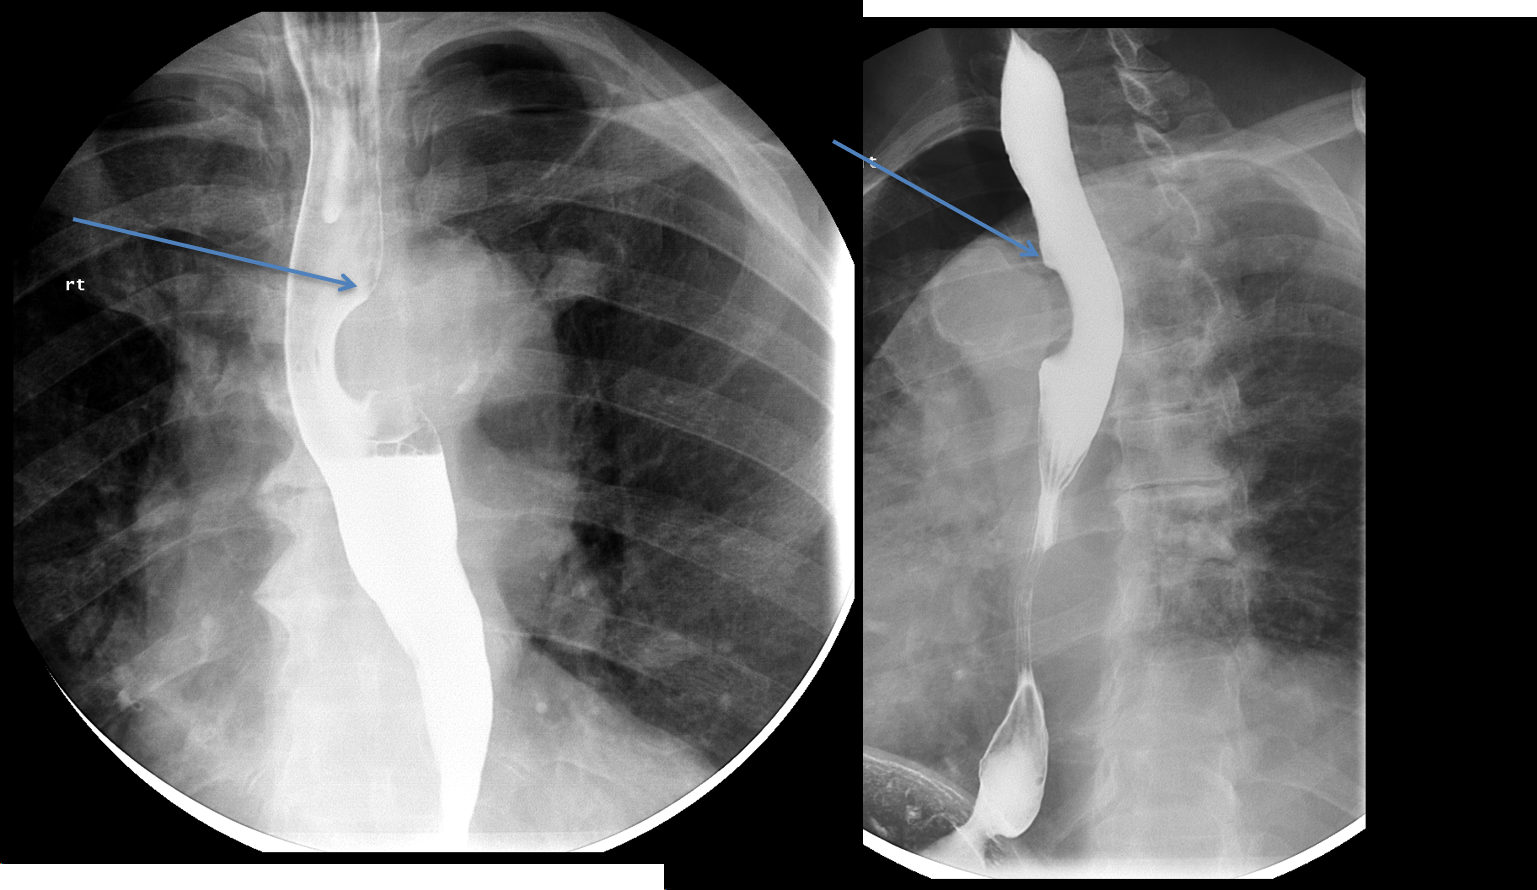

Submucosal esophageal masses

- The differential of esophageal masses is different depending on appearance

Submucosal lesions usually have smooth, obtuse margins with the esophagus, like this case.

- Differential is broad, and includes leiomyoma, duplication cyst, GIST, as well as hematoma.